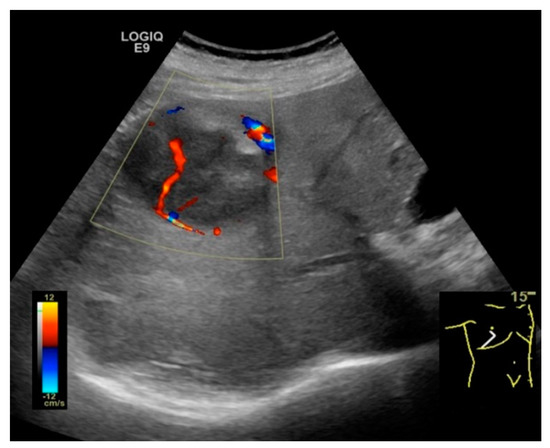

2.2. NAFLD-Related HCC: Could Conventional and Doppler US Differentiate between Focal Liver Lesions (FLLs)?

- Tochio, H.; Kudo, M. Afferent and efferent vessels of premalignant and overt hepatocellular carcinoma: Observation by color Doppler imaging. Intervirology 2004, 47, 144–153. [Google Scholar] [CrossRef] [PubMed]

- Kudo, M.; Tochio, H.; Zhou, P. Differentiation of hepatic tumors by color Doppler imaging: Role of the maximum velocity and the pulsatility index of the intratumoral blood flow signal. Intervirology 2004, 47, 154–161. [Google Scholar] [CrossRef]

- Salvatore, V.; Bolondi, L. Clinical impact of ultrasound-related techniques on the diagnosis of focal liver lesions. Liver Cancer 2012, 1, 238–246. [Google Scholar] [CrossRef] [PubMed]

| Doppler US | Abnormal waveforms of the hepatic veins (normal triphasic pattern disappears) [81] Velocity of the portal flow (flow peak maximum velocity and mean flow velocity) and the portal vein pulsatility index (VPI) are significantly lower in patients with fatty liver when compared to the controls; it also corelates with the severity of the fatty liver [82] |